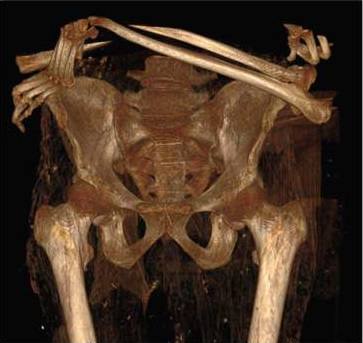

8

Vista frontal de la reconstrucción en 3D de la pelvis; en la parte superior se observan los brazos cruzadosUCM / Archimadrid